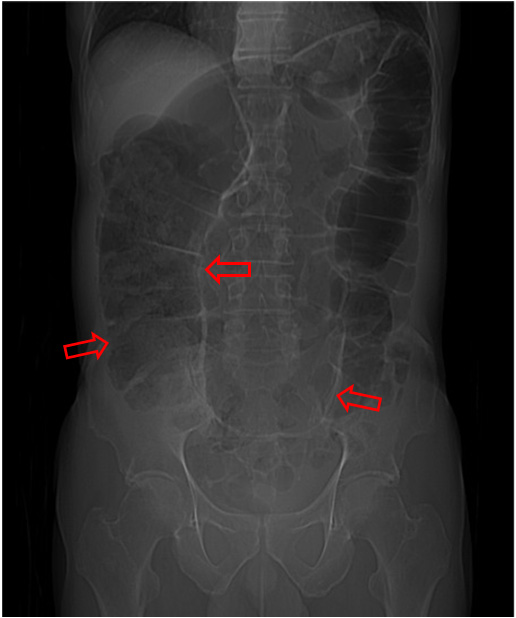

SIGNO DE LAS LÍNEAS CONVERGENTES

Es un signo de vólvulo de sigma que se ve al tiempo que el Signo del grano de café, pero no referido al luminograma del sigma dilatado sino a las paredes sigmoideas. Se trata de tres líneas que delimitan la pared del sigma (flechas), dos laterales y una central, más gruesa, formada por la aposición de las paredes de las dos partes del sigma, la que asciende y la que desciende. Las tres líneas convergen en la pelvis en la zona de la volvulación.

La imagen ha sido cedida por Federico Cáceres, de su blog Radiodiagnosticando:

http://radiodiagnosticando.com/2014/07/11/caso-volvulo-de-sigma/.

Este signo se ha denominado también Signo de Frimann-Dahl.